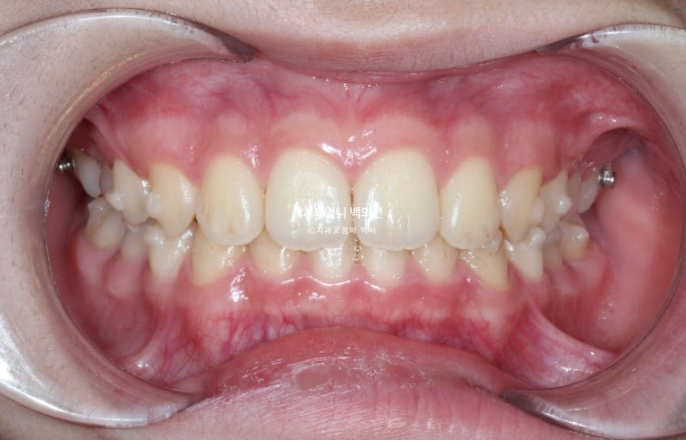

24.03

작년 봄, 교정치료를 위해 내원한 만 10세 어린이입니다.

위 앞니가 아랫니를 많이 덮어 깊게 물리는 과개교합이 보입니다.

위 앞니 돌출이 보입니다.

남아있는 유치 두 개가 가위교합입니다.